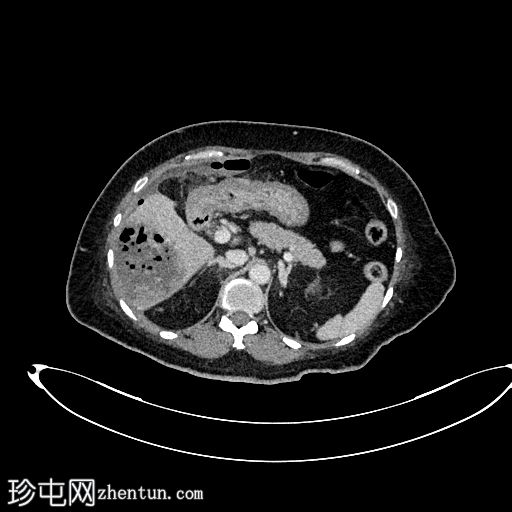

超声检查

肝胆系统

肝脏第6和第7段可见多个高回声气体腔,遮挡肝脏后部

肝脏其他部位形态及回声纹理正常

胆总管扩张,无结石,肝内胆管未见扩张

其他方面正常无游离液体

超声表现符合气肿性肝脓肿。数小时后进行的肝脏增强 CT 多期扫描显示气肿性肝脓肿破裂。